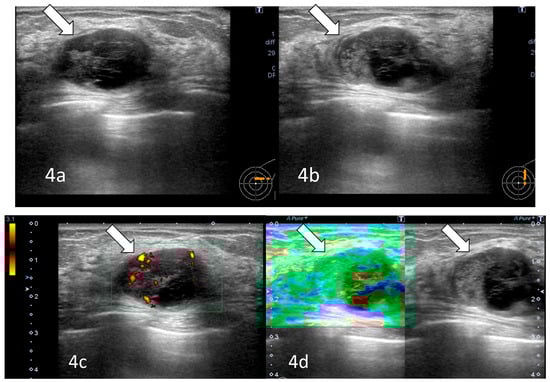

Radiological examination after 11 years: Screening mammography showed a newly visible dense, ill-defined mass in the upper outer quadrant of the left breast (Figure 3). Ultrasound demonstrated a 27 mm oval hypoechoic mass with central low and peripheral iso-to-hyperechoic areas and posterior enhancement (Figure 4a,b). Color Doppler imaging revealed abundant peripheral vascularity (Figure 4c). Strain elastography showed mildly reduced strain (Figure 4d). On MRI, a well-circumscribed round mass with high signal intensity was observed on fat-suppressed T2-weighted images (Figure 5a). Dynamic contrast-enhanced imaging demonstrated spatially heterogeneous enhancement spreading from the periphery to the center, with a fast-plateau enhancement pattern in the peripheral portion and a medium persistent enhancement pattern in the central portion (Figure 5b,c). The mass showed high signal intensity on diffusion-weighted imaging and high apparent diffusion coefficient (ADC) values (Figure 5d,e). The mass was classified as Breast Imaging Reporting and Data System category 4B, and ultrasound-guided vacuum-assisted biopsy was performed.

Figure 4. Ultrasonography (after 11 years): A 27 mm oval hypoechoic mass with central low and peripheral iso- to hyperechoic regions and posterior enhancement (arrows) was observed (a,b). Color Doppler imaging showed abundant peripheral flow (arrow) (c), and strain elastography showed mildly reduced strain (arrow) (d).